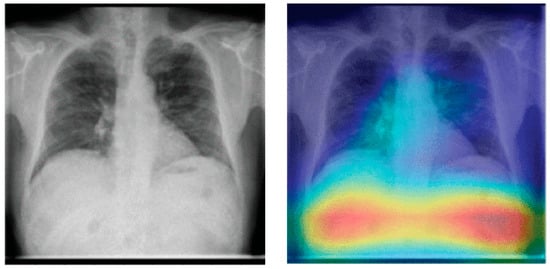

Catalá et al. [121] have experimented with background expansion and lung exclusion in CXR images. Background expansion means a background is gradually added to initial lung-only images. Figure 13 depicts an example of background expansion. Ideally, the AUC ROC should not be affected by background expansion. However, empirical results obtained indicate a significant AUC ROC increase when a background is expanded in two of three datasets used. This means that features outside the lung area often play a critical role in correct predictions.

Figure 13.

Example of background expansion (all images taken from [121]). From (a–c) the background is gradually expanded.

Figure 14 depicts an example of lung occlusion, i.e., the gradual removal of the lung area from CXR images. Ideally, the AUC ROC should go down close to 0.5 for the complete occlusion of the lung. However, an AUC ROC of up to 0.88 has been achieved for full lung occlusion. This is quite remarkable as this means that even without considering lung tissue, the model is able to correctly predict the class of the CXR image. These findings may imply that the results reported in various research studies on the performance of pneumonia detection models may be too optimistic and may not be a true representation of the capabilities of those models.

Figure 14.

Example of lung occlusion (all images taken from [121]). From (a–c) the lung area is gradually occluded.